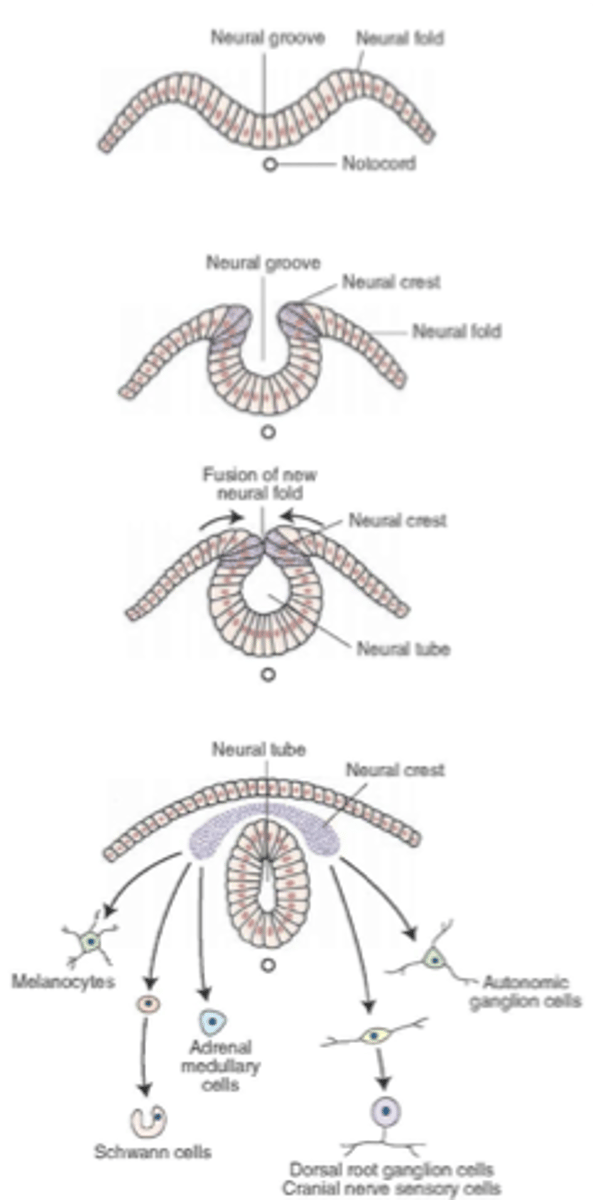

what are the cells that appear along the edge of the neural plate as it elevates?

neural crest cells

what are ganglia, meninges, and Schwann cells derived from?

these arise from the neural crest cells

the fusion of the neural folds begins in the __________ region then proceeds ___________ and __________ to form the neural ________

cervical, cranially, caudally, tube

the (caudal/cranial) neuropore will normally close on day ____ before the (caudal/cranial) neuropore which closes on day ____

cranial, 25, caudal, 28

the narrow (caudal/cranial) portion of the neural tube will form the spinal cord while the broad (caudal/cranial) portion forms the brain vesicles

caudal, cranial